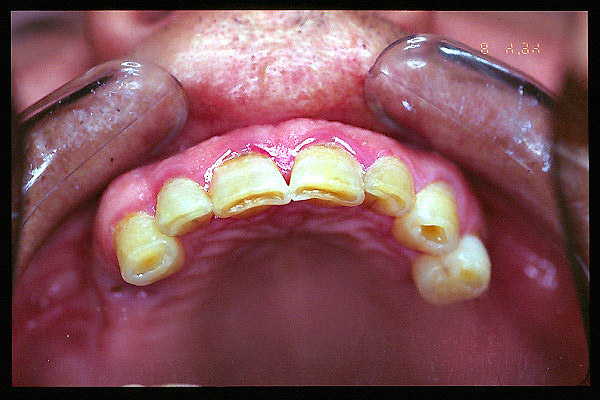

CM Extrusión de incisivos inferiores por falta de contactos oclusales